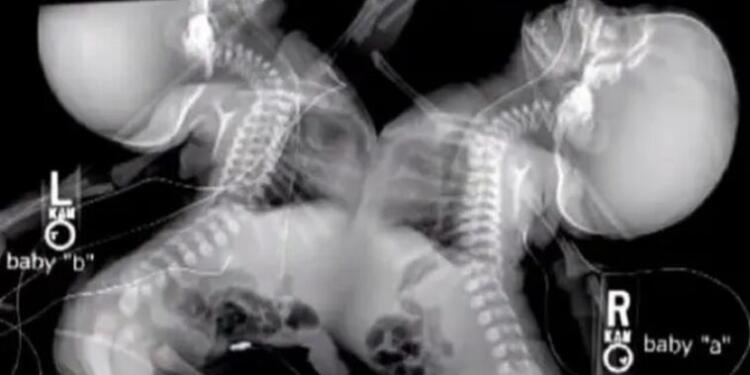

Τα δίδυμα ήταν ενωμένα στο στέρνο τους, στο διάφραγμα, στο συκώτι και στην μεμβράνη γύρω από την καρδιά. Ο φόβος ότι τα μικρά κορίτσια δεν θα επιβίωναν τον διαχωρισμό, οδήγησε τους γιατρούς να συμβουλέψουν την Shellie να τερματίσει την εγκυμοσύνη.

Σύμφωνα με το CNN, “Το συνολικό ποσοστό των ενωμένων διδύμων κυμαίνεται ανάμεσα στο 5% και στο 15%. Στο 75% αυτών των περιπτώσεων επιβιώνει μόνο το ένα παιδί, μετά από εγχείρηση.